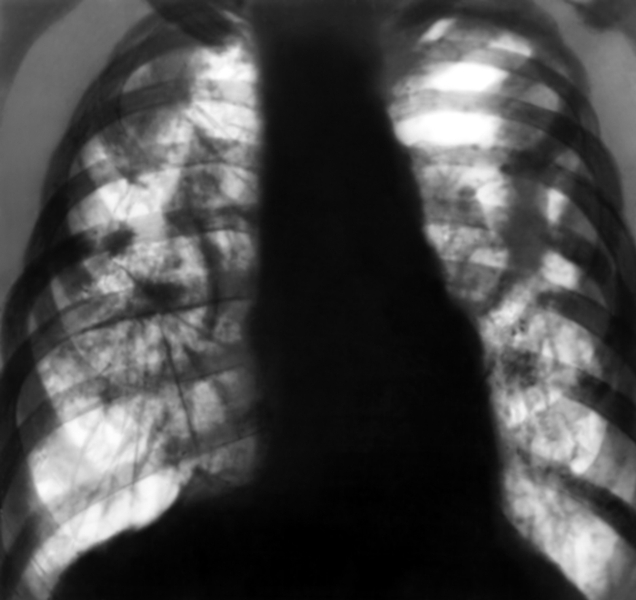

- рентгеноскопия и –графия органов грудной клетки – ведущий метод при обнаружении пневмокониозов;

При рентгенологическом исследовании в легких обнаруживают тени – это маленькие узелки и образовавшиеся при их слиянии узлы с четкими очертаниями. Процесс начинается с единичных мелких образований до 1-1,5 мм в диаметре. Для пневмокониоза характерно то, что такие узелки более-менее равномерно распределены по всей легочной ткани. В ряде случаев узелков бывает больше справа (правый бронх короче и шире, чем левый – благодаря этому создаются лучшие условия для проникновения через него пыли в легкое). У пациента, трудящегося на производстве, связанном с вдыханием пыли, важно проводить повторные рентгенографии – так называемое исследование в динамике. Благодаря повторному исследованию фиксируется увеличение размеров узелков (до 10 мм в диаметре). Нарастание количества узелков наблюдается не всегда.

В далеко зашедших случаях на рентген-снимках наблюдается массивное прорастание легкого соединительной тканью – оно приводит к таким четко выраженным на снимках изменениям, как деформация:

- легочной ткани;

- бронхиального дерева;

- органов средостения.

Также характерный признак – вкрапления в лимфатических узлах (из-за оседания в них извести).